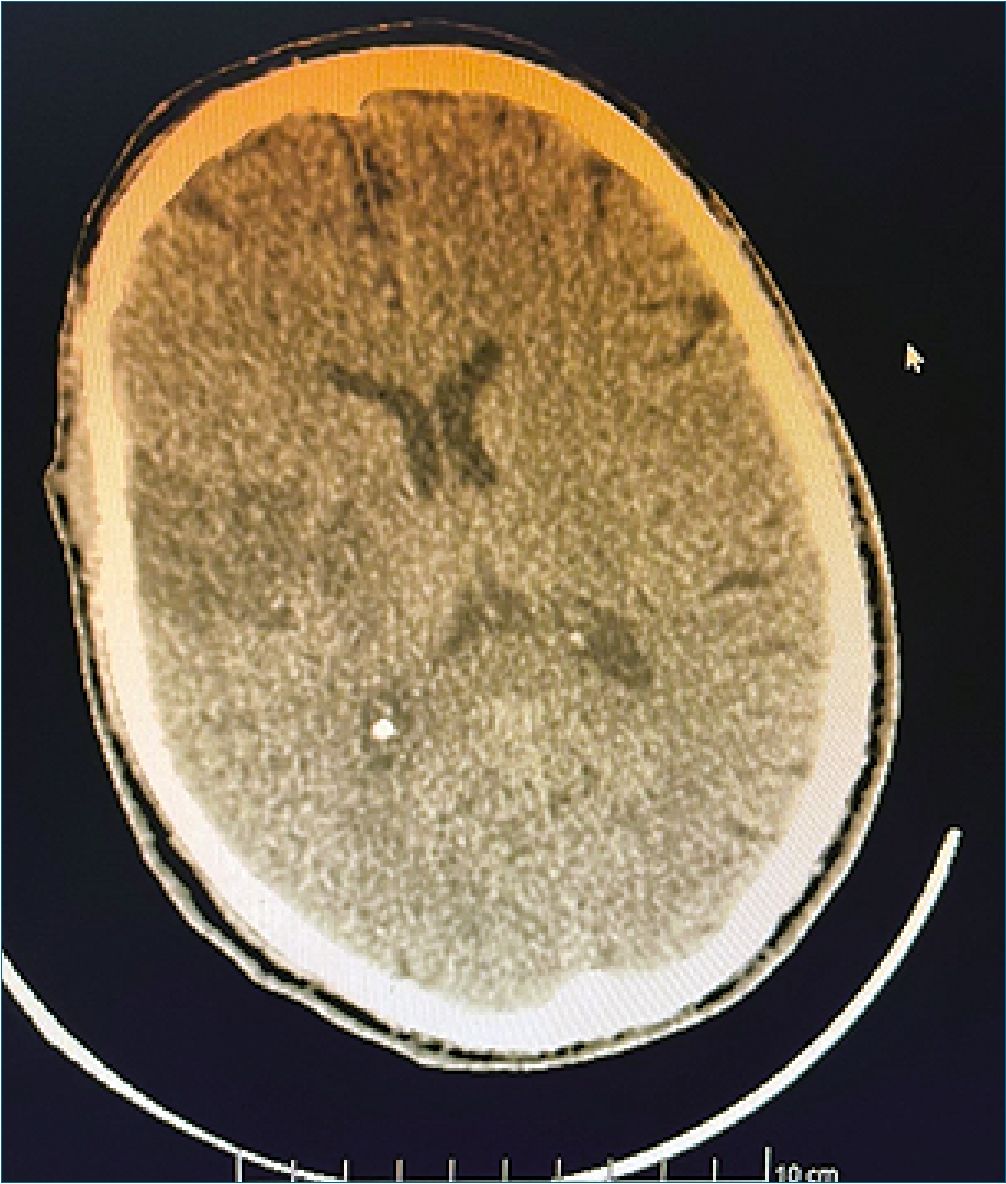

Control tomográfico a las 24 h evidencia hipodensidad subcortical y periventricular derecha que afecta la convexidad de la circunvolución parietal ipsilateral, lo cual sugiere una isquemia configurada (Figura 2). En la evolución paciente sin cambios clínicos, persistiendo con síndrome piramidal izquierdo proporcionado, con parálisis facial central y corticobulbar en etapa flexoespástica y Babinski a izquierda. El planteo diagnóstico fue infarto cerebral derecho de naturaleza tromboembólica. A los 15 días es dado de alta a domicilio.

Figura 2. TAC control a las 24 h, muestra configuración del área de isquemia subcortical parietal derecha.